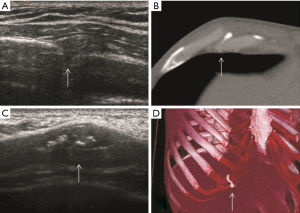

US findings of tendinous and muscular lesions injuries include disruption, absence and retraction of the tendon and muscle fibres, as well as haematoma. Immediately after injury, a haemorrhage is hypoechoic; however, it will become heterogeneously echogenic with clot formation and organization into a haematoma.

A normal pectoralis major tendon should have uniform low signal intensity on MR imaging. Like US (34), tears of the pectoralis major tendon seen on MR imaging exhibit different degrees of tendon abnormality, depending on the degree of injury. A grade I strain of the muscle belly will have feathery intramuscular fluid-sensitive signal intensity, which represents oedema and/or haemorrhage. Grade II injury will appear as a partial tear with an intramuscular hematoma, while grade III injury has a complete tear with possible retraction (Figures 11-13). As a matter of fact, a partial tear involving only the posterior sternal segments, the anterior clavicular head and tendon will be intact, with the long head of the biceps tendon in place. With complete tears involving both the sternal head and the clavicular head, however, there will be disruption of the entire tendon, with anterior displacement of the long head of the biceps tendon (35).